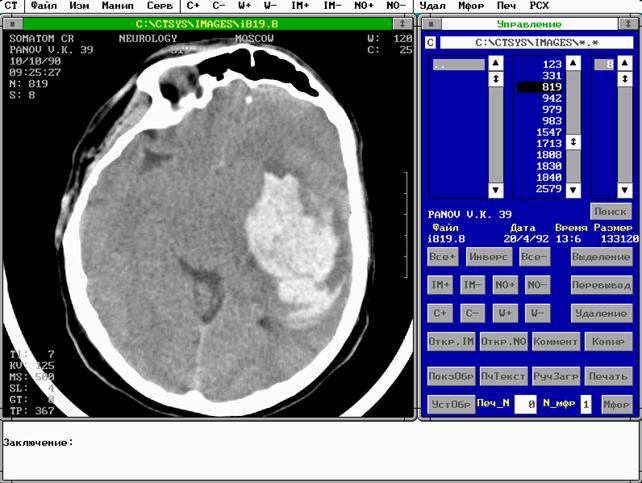

Нормальное увеличение плотности мозга на компьютерной томограмме после введения контрастного вещества связано с внутрисосудистой концентрацией йода. Можно получить изображение сосудов диаметром до 1,5 мм, если уровень йода в крови составляет примерно 4 мг/мл и при условии, что сосуд расположен перпендикулярно к плоскости среза. Наблюдения привели к выводу, что контрастное вещество накапливается в опухолях. [№5, стр. 17-19], [рис.2]

Рис 2. Пример КТ снимка, полученного в программе CTsoft .[№6, стр2] ГЛАВА II. МАГНИТНО-РЕЗОНАНСНАЯ ТОМОГРАФИЯ